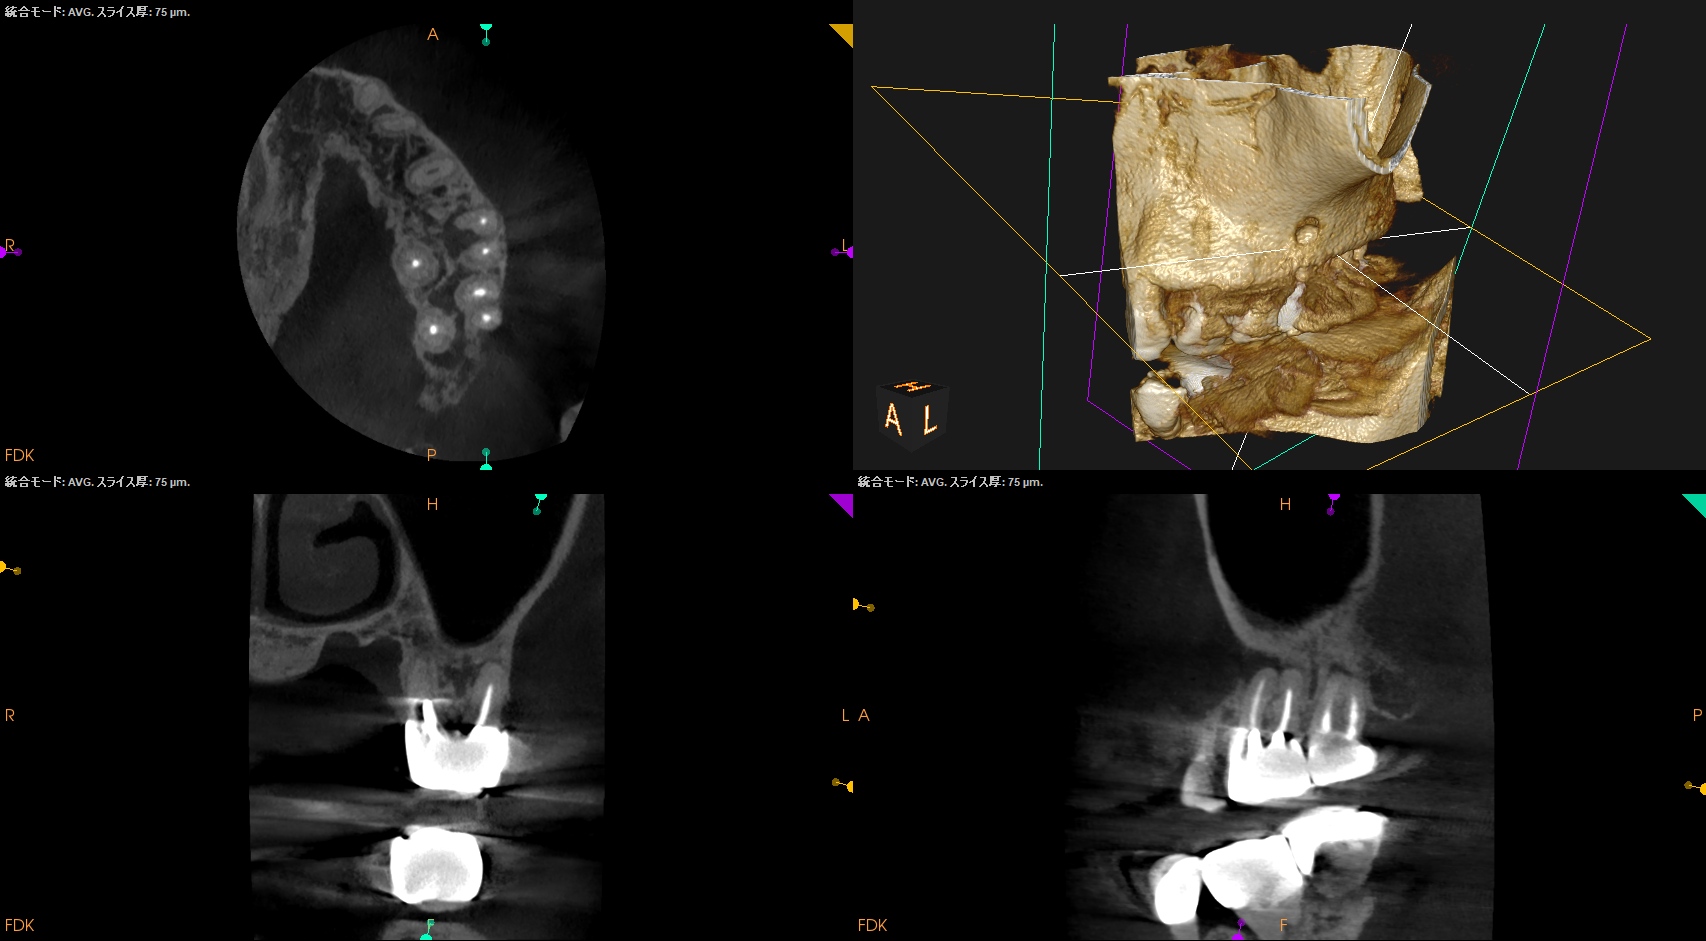

Pre-op Endo test(2025.4.14)

MB2は確実に存在するが石灰化が進み穿通できるか?わからない。

また、Sinus tractが根尖孔外細菌感染の可能性もある。

このことから再根管治療よりも外科治療の方に軍配が上がるだろう。